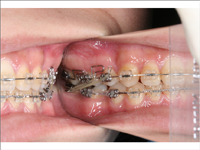

デーモンシステム・クリッピーシステム

新しいコンセプトの装置です。シャッターでワイヤーを固定することで歯の移動が速くなる特徴があります。

新しいコンセプトの装置です。シャッターでワイヤーを固定することで歯の移動が速くなる特徴があります。

2)矯正中の状態